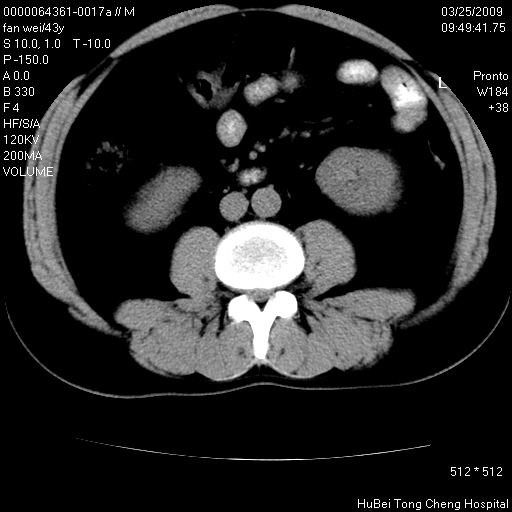

患者 男,43岁。左侧腰部不适两天。平素健康。无家族遗传病史。

双肾ct轴位平扫+增强扫描(层厚10mm,螺距1.0,重建间隔10mm),图像如下:

双肾多发性囊肿

左肾体积变大,支持多囊肾。

双侧多囊肾!